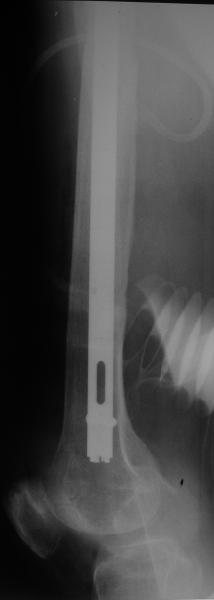

Female, rheumatoid, THA in 2003, car accident in 2006, failed plating. Nailing in Oct 2007. The nail is solid with hollow proximal part where the stem is docked. Last images are in 1 year after

nailing.

Спасибо за обсуждение. После нескольких дней тракции аппаратом сделали. Попытка закрытой репозиции не удалась из-за смещения по ширине, мешали фрагменты цемента. После их удаления репозиция получилась. Еще убрали немного цемента с ножки по латерльной стороне, чтобы обнажить 40-50 мм ее дистальной части, для плотной посадки гвоздя. Дальнейшее введение гвоздя было несложным. Протез показался нам стабильным в проксимальной части как латерально, так и медиально. Картинки в приложении.

THX for the discussion. After few days of traction by ex-fix the surgery was performed. An attempt of closed nailing was unsuccesful because of fragment translation, which was blocked by cement fragments. After removal of broken cement pieces reduction was reached "automagically". Also some cement from lateral part was removed by

chisel to expose distal 40-50 mm of the stem to allow tight fit of the nail. Further fixation by the nail was pretty easy and straightforward. Images attached. The stem looked stable in its proximal part both laterally and medially. Comments/critics are welcome.